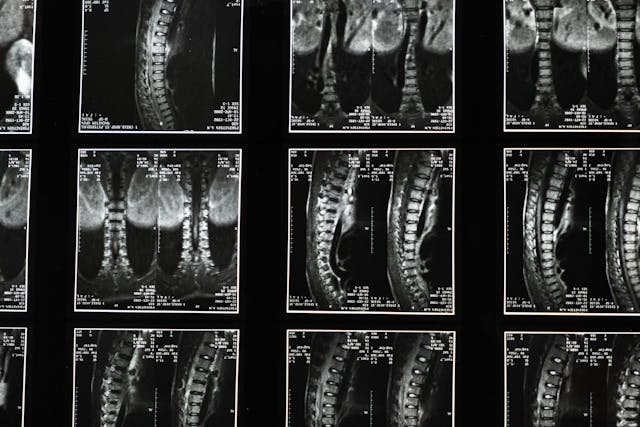

Spinal Injury Care

At Angel Care Group, our Spinal Injury Care service is designed to support individuals in adapting to life after a spinal injury, promoting independence, mobility, and an improved quality of life. Our highly trained caregivers provide specialized assistance tailored to each client’s physical and emotional needs, ensuring a safe and supportive environment.